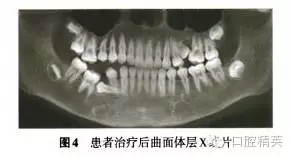

診斷:安氏Ⅲ類亞類錯牙合畸形,5V、5V阻生。治療方案:①拔除V,V,清理V囊腔;②牽引5至正常牙列;③試牽引5,不排除牽引失敗的可能;④使用種植體支抗防止鄰牙壓低和對牙合牙伸長;⑤糾正右側(cè)后牙開牙合,若654粘連導(dǎo)致正畸治療無效,則需調(diào)整治療方案。拔除埋伏乳磨牙時,錐形束CT確認下頜神經(jīng)管位于阻生V根分叉下方(圖3),5牙根位于43舌側(cè)。手術(shù)順利拔除埋伏阻生的V、V,8個月后曲面體層x線片示牙槽骨愈合良好,可見4顆第三磨牙牙胚(圖4)。但患者家長放棄牽引治療。